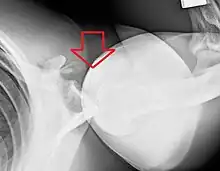

An anterior dislocation of the shoulder

Anterior dislocation of the right shoulder. AP X ray